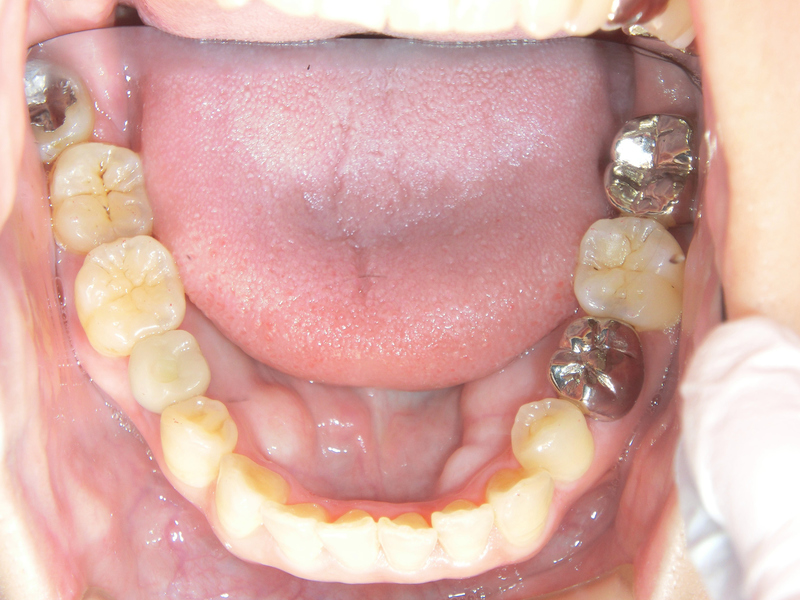

インプラントが骨にしっかりと固定されたら、今度は土台となる部位や被せ物、つまり「歯」として機能する部位をつけます。

向かって左奥から4番目の歯がインプラント治療による歯です。とてもきれいですね。このように自分の歯のように自然な仕上がりが期待できますが、噛み合わせや噛む力をどれだけいれることができるか、は少しずつ様子をみていくこととなります。

なお、レントゲンではこのように見えることとなります。